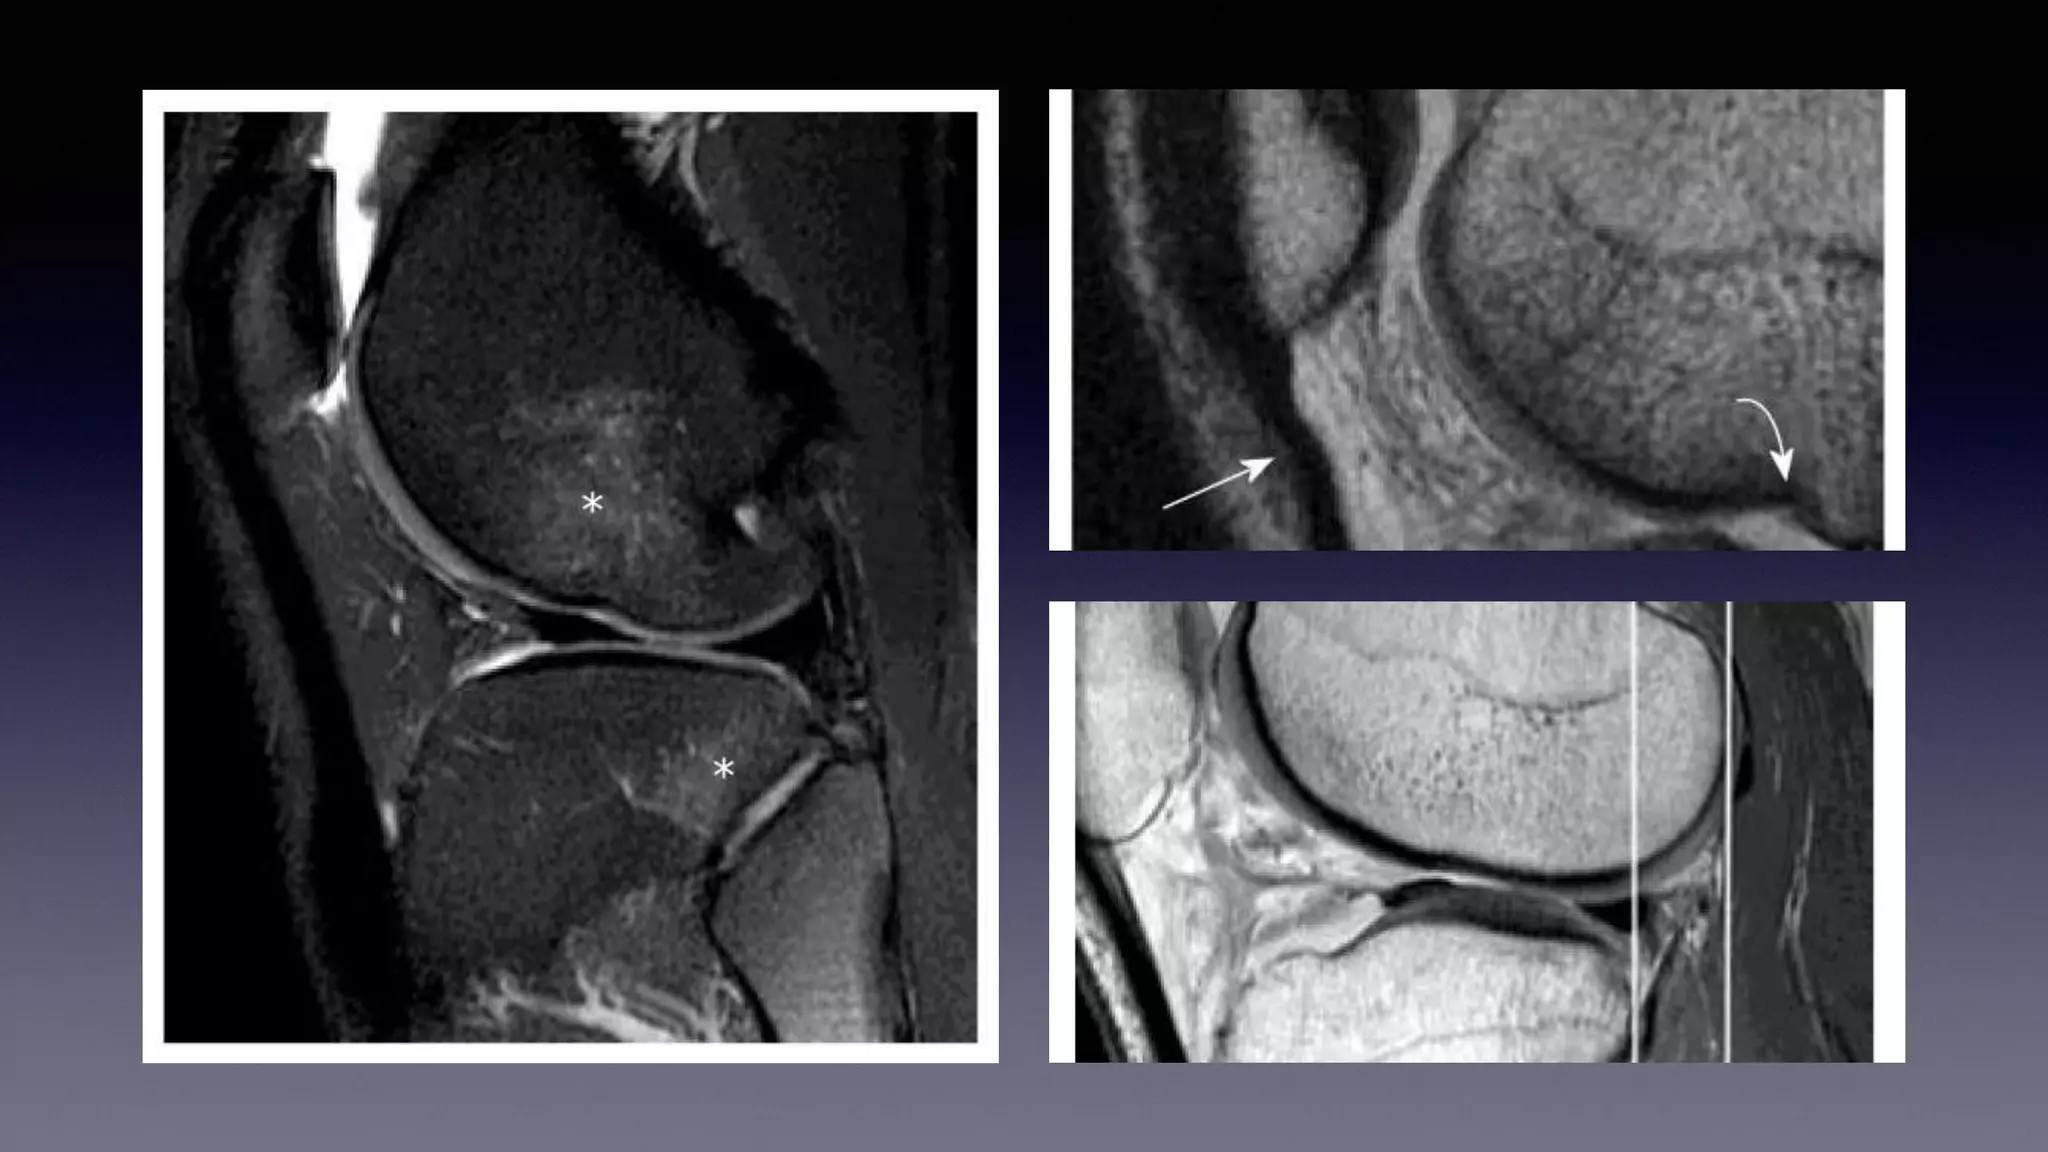

This document discusses using MRI to diagnose ligament injuries in the knee. It begins with an overview of MRI anatomy of the knee and expected pathology. It then discusses specific ligaments like the ACL, PCL, MCL and LCL. For the ACL, it shows images of acute tears, chronic tears and intrasubstance tears. It emphasizes knowing the knee anatomy well and correlating any abnormalities seen with clinical findings in order to apply the appropriate treatment.